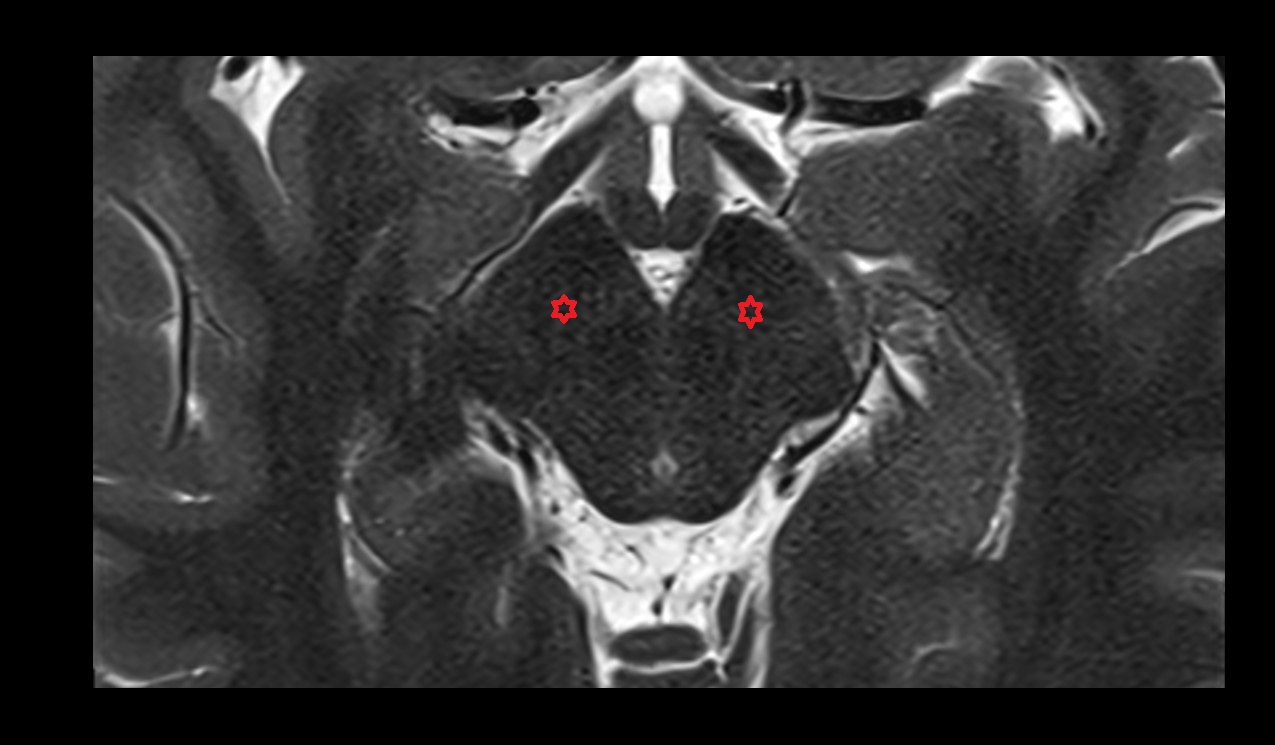

- Hippocampus